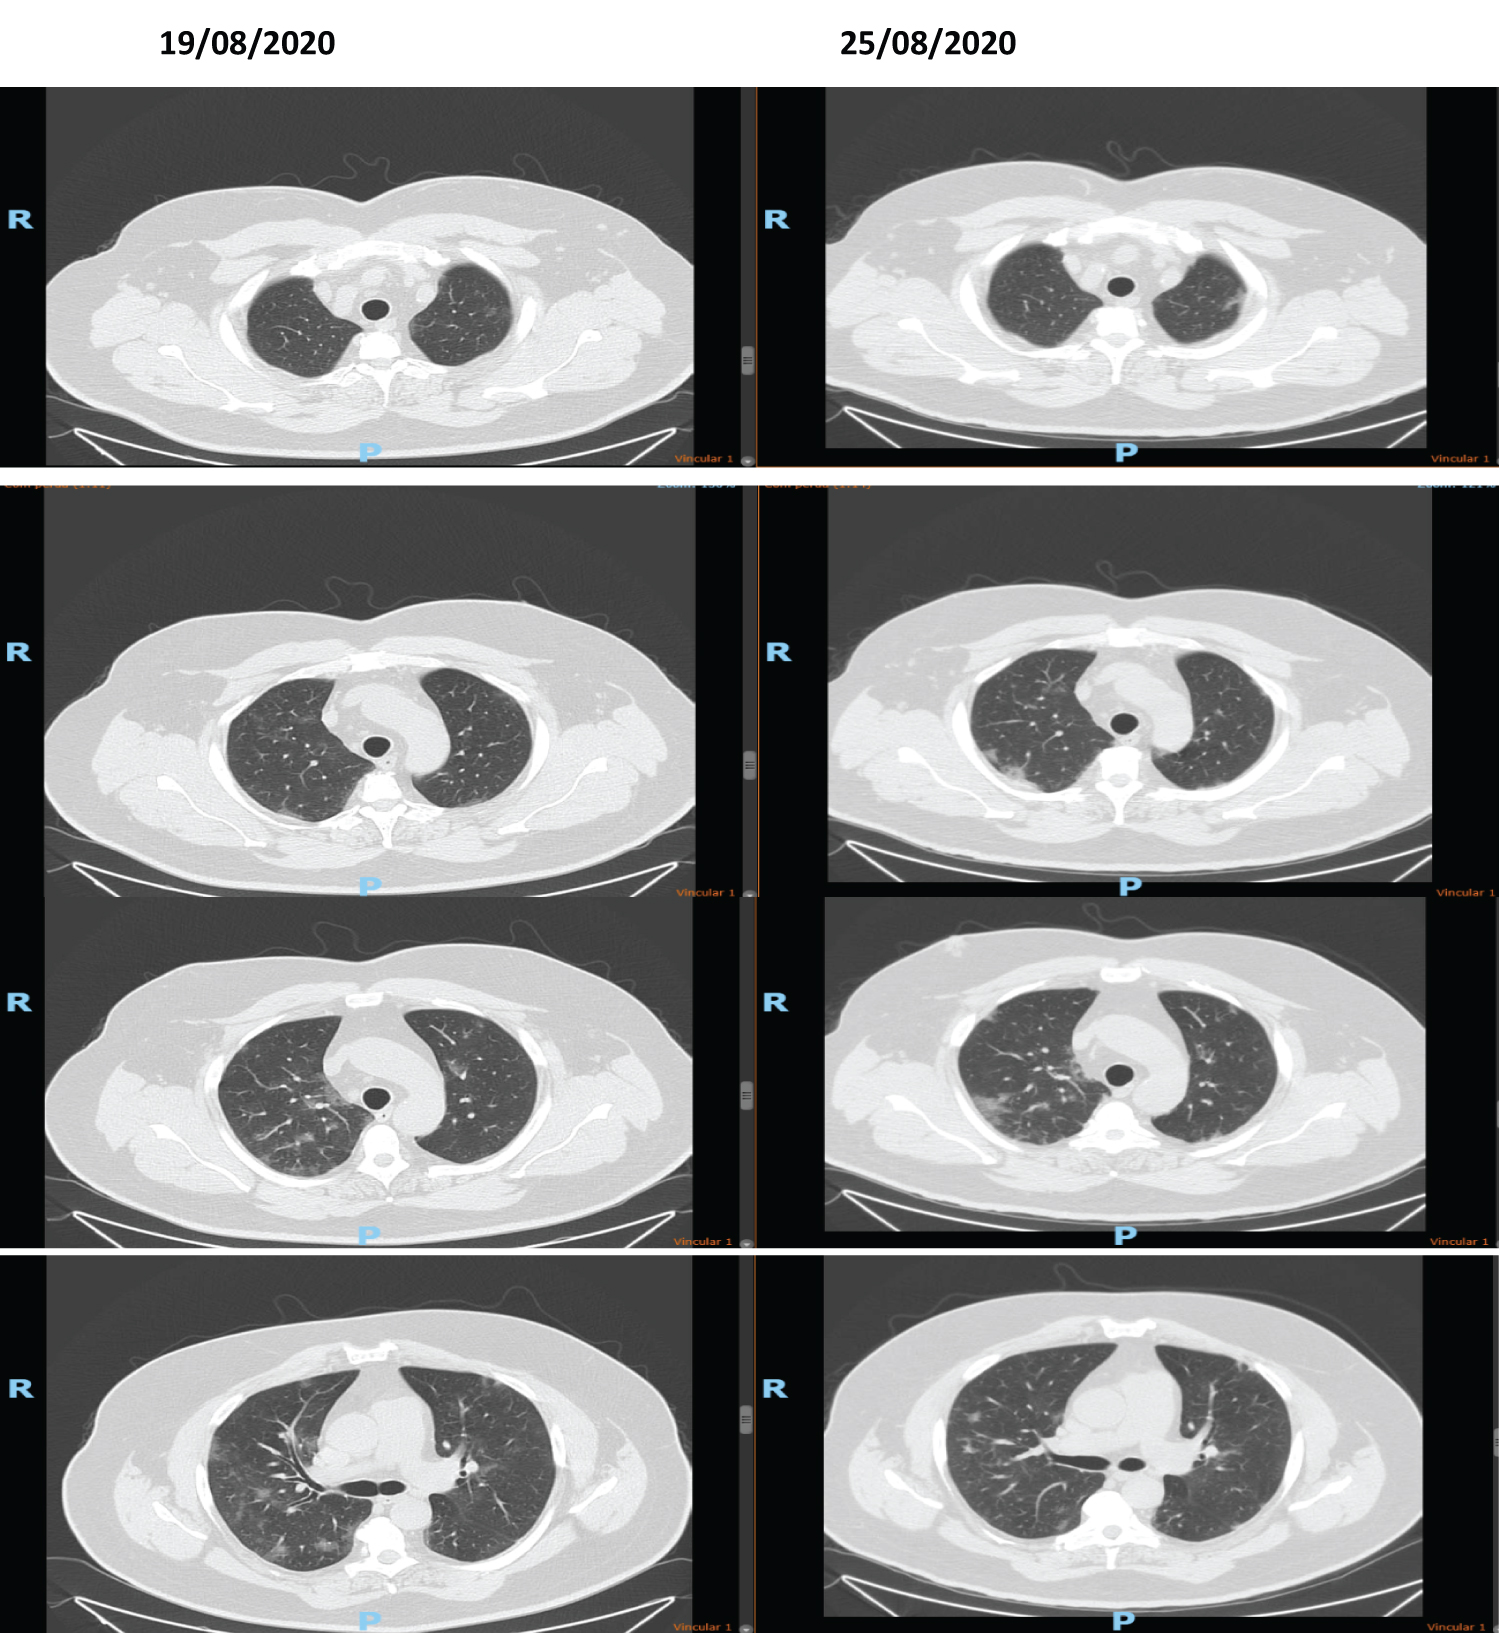

We have to keep in mind that we are still facing a war against an unknown virus. We are building knowledge and are now miles away from where we started. Standard lung images obtained when patients with systemic symptoms were readmitted (sometimes repeatedly) to Hospital showed acute Covid-19 mimicking findings. Some of those images are attached in Figures 6a-l.

Figure 6A-D: After ICU stay and orotracheal intubation and readmitted in the Infectious Diseases wards. Obese and or Diabetic patients after 14 days of disease. (14-40 days). Observe the "heavy" pattern of the images with opacities denoting extensive posterior atelectasis or even condensation in the pulmonary parenchyma in a diffuse manner. This tomography is different from the acute COVID-19 in Figure 1, where we have a ground grass pattern that is lighter and more tenuous. We are readmitting patients who already arrive with a "heavy" image pattern with new decompensation. This patient is not acute COVID-19; he is only exacerbating a disease, usually a vasculitis triggered by acute SARS-CoV-2 infection. In this phase, the patient responds better to corticosteroids and the intubation time is usually shorter since there is an evident autoimmune component. Differentiating between acute COVID-19 or COVID-19 in a critical phase (cHIS) is essential, as the pathophysiology of the disease changes: Acute COVID-19: viral action. Chronic COVID-19: Immunosuppression and autoimmunity phase. Two data are necessary to understand whether the case is acute or not: 1- To ask the patient whether he has had respiratory decompensations in the last months and what the recurrence is or whether there has been any change in his behaviour or pain, or tiredness in the last months - this can mean COVID-19 that has not been previously diagnosed; 2- Observing tomography: heavy hard images with laminar atelectasis and thickening of bronchi and bronchioles: Chronic phase; A lighter image of infiltration in frosted glass: acute COVID-19. The pattern of pneumonia after COVID-19 has been acute fibrinous and organizing pneumonia (AFOP) that is a histological pattern characterized predominantly by the presence of intra-alveolar fibrin in the form of fibrin "balls" within the alveolar spaces, with a patchy distribution, and organizing pneumonia. E-H: Patient, 46-years-old, HIV+ with viral load always undetectable and CD4+ always higher than 600, started skin lesions associated with pruritus without improvement. He mentions having seen three other doctors who considered Kaposi's Sarcoma hypothesis. However, when asked about his last semester, the patient reported an essential change in mood. I note that the lesions can be due to mastocytosis after COVID-19 or even vasculitis. We started Dexamethasone equivalent to a 250 mg dose of Methylprednisolone for 3 days and de-escalating the dose for another 5 days. It evolves on the first day with many tremors that improved after the second day. It also evolves with the improvement of skin lesions. I associated acetylsalicylic acid thinking about platelet activation in case of vasculitis and request new tests. I: Tomography shows ectasia of the ascending aorta, accentuation of the centrilobular stipple and presence of bronchial thickening; CD8 + = 270 and CD4 + = 197. Tomography findings appear in vasculitis and other diseases of the parenchyma. Possible diagnoses: Vasculitis, mastocytosis. The patient will be reassessed for new Cd4+ and CD8+ and skin biopsy collections if there are new lesions. J-L: Young, male, 19-years-old. Admitted to HSPE due to dyspnoea for more than 8 days. IgM and IgG positive. At the time, we questioned granulomatosis with polyangiitis, but we were surprised to see a positive sputum smear for Mycobacteria tuberculosis. Reanalysing, this case should be recalled and seen by a new aspect: COVID-19 + induced vasculitis + activation of latent tuberculosis by immunoparalysis. View Figure 6